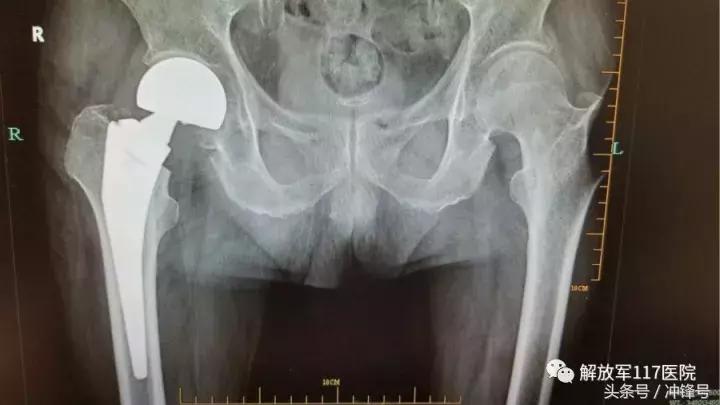

术后X光片

“手术风险高,难度大,要求我们一定要谨慎谨慎再谨慎。”侯振海团队如临大敌,不敢有丝毫放松。仔细为老人评估病情,排除各项禁忌;协调放射科和超声科迅速为老人作全面检查,完善诊断;详细为老人查体,掌握不适症状。为尽快手术,解除老人病痛,第一时间开通绿色通道,加快术前检查流程,于入院后13小时完成全部术前检查及各项评估。经综合分析,右股骨颈头下型骨折是引起老人疼痛和活动受限的“罪魁祸首”,最终决定为其行“右人工股骨头置换术”。手术如期进行。麻醉科主任吕文艳全程指导麻醉全过程,侯振海副主任亲自主刀,在麻醉和手术团队的通力协作下,手术进展十分顺利,仅用时35分钟即完成整个手术,术后老人疼痛明显减轻,生命体征平稳。但侯振海团队依然不敢大意,在接下来的几天中,侯振海副主任、范亮全主治医师以及汤霄朕住院医师每天都轮流到病房查看老人病情,定期伤口换药,并针对性作抗感染、抗凝、护胃、化痰等对症治疗。

在医护人员的精心呵护下,老人恢复明显。于术后5天首次下地,术后10天可在搀扶下实现站立,并于术后11天顺利出院。